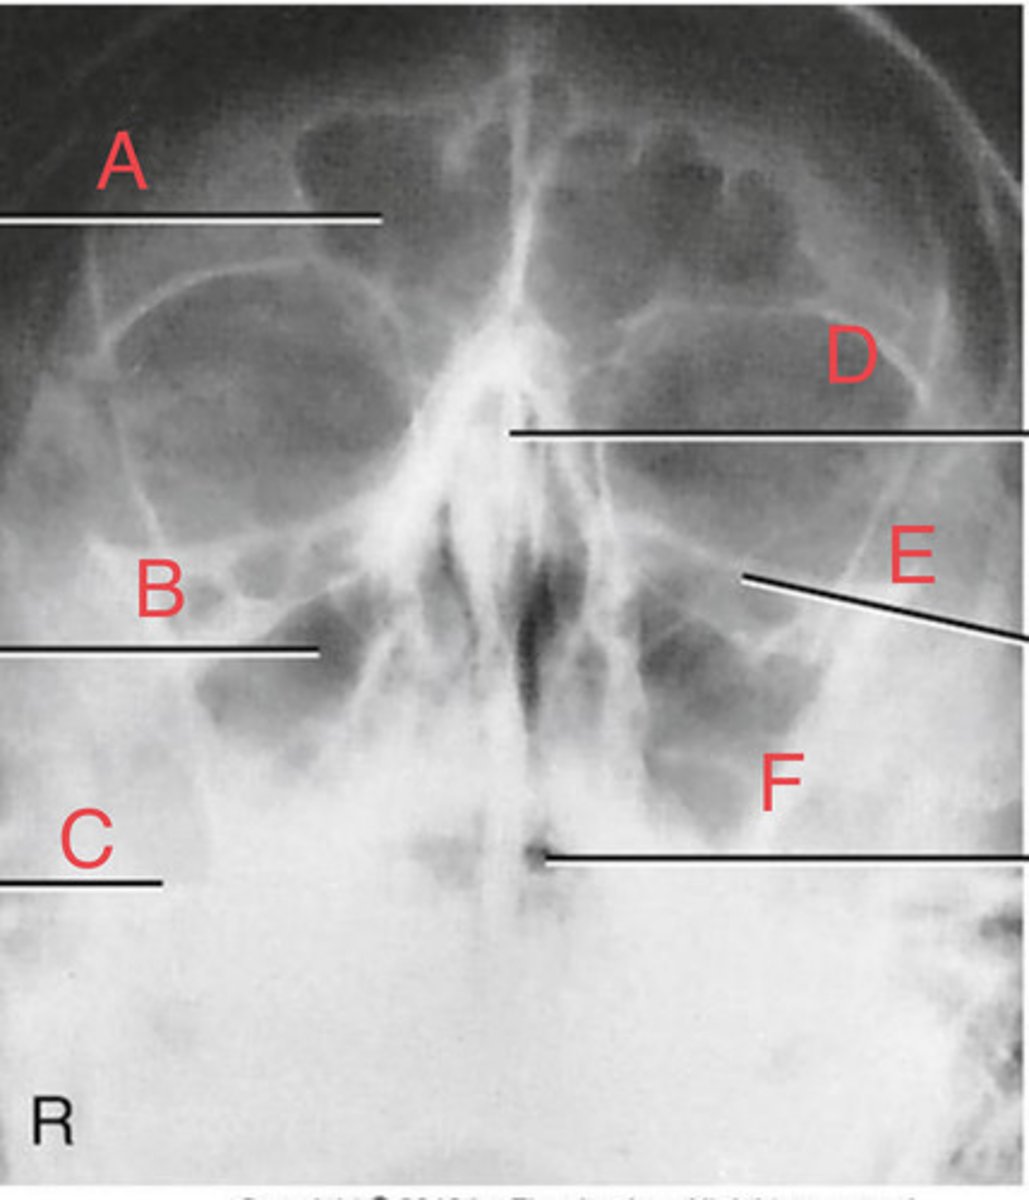

Waters sinus method

What projection?

r. frontal sinus of the frontal bone

A.

R. Maxillary sinus of maxilla

B.

R. petrous ridge of temporal bone

C.

bony nasal septum

D.

L. inferior orbital fissure of sphenoid bone

E.

Sphenoid sinus of sphenoid bone

F.

bony nasal septum

E.